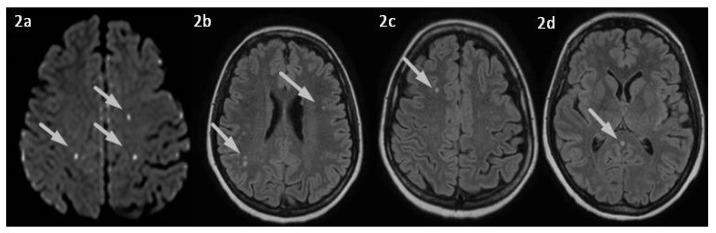

Cerebral venous thrombosis (CVT) is a rare cause of stroke, particularly in young adults. Several known thrombophilic conditions may lead to an increased CVT risk. Interestingly, few cases in the literature have reported an association between CVT and thyrotoxicosis. Here, we describe the case of a young woman with CVT and concomitant thyrotoxicosis, without any other known prothrombotic conditions. We also performed a literature review of CVT cases and hyperthyroidism, searching for all articles published in peer-reviewed journals. We identified 39 case reports/case series concerning patients with CVT associated with thyrotoxicosis, highlighting, in most cases, the association with additional known prothrombotic factors. We then discussed the possible mechanisms by which hyperthyroidism could underlie a pro-coagulative state resulting in CVT. Thyroid disease might be a more common prothrombotic risk factor than expected in determining CVT. However, in most cases, a coexistence of multiple risk factors was observed, suggesting a multifactorial genesis of the disorder. We hope that this work may alert clinicians to consider thyrotoxicosis as a potential risk factor for CVT, even in patients who apparently have no other pro-coagulative conditions.

脑静脉血栓形成(CVT)是一种罕见的中风病因,尤其在年轻人中。几种已知的血栓形成倾向状况可能会增加CVT风险。有趣的是,文献中很少有病例报告CVT与甲状腺毒症之间存在关联。在此,我们描述了一名患有CVT并伴有甲状腺毒症的年轻女性病例,该患者无任何其他已知的血栓前状态。我们还对CVT病例和甲状腺功能亢进进行了文献综述,检索了同行评审期刊上发表的所有文章。我们确定了39例关于CVT与甲状腺毒症相关患者的病例报告/病例系列,在大多数情况下,突出了与其他已知血栓前因素的关联。然后我们讨论了甲状腺功能亢进可能导致促凝状态进而引发CVT的潜在机制。在导致CVT方面,甲状腺疾病可能是一个比预期更常见的血栓前风险因素。然而,在大多数情况下,观察到多种风险因素并存,提示该疾病具有多因素发病机制。我们希望这项工作能提醒临床医生,即使在明显没有其他促凝状况的患者中,也要将甲状腺毒症视为CVT的潜在风险因素。